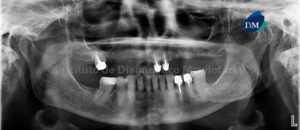

Paciente masculino de 27 años de edad acude al Instituto de Diagnóstico Maxilofacial por evaluación de terceras molares. Motivo por el cual se le realiza